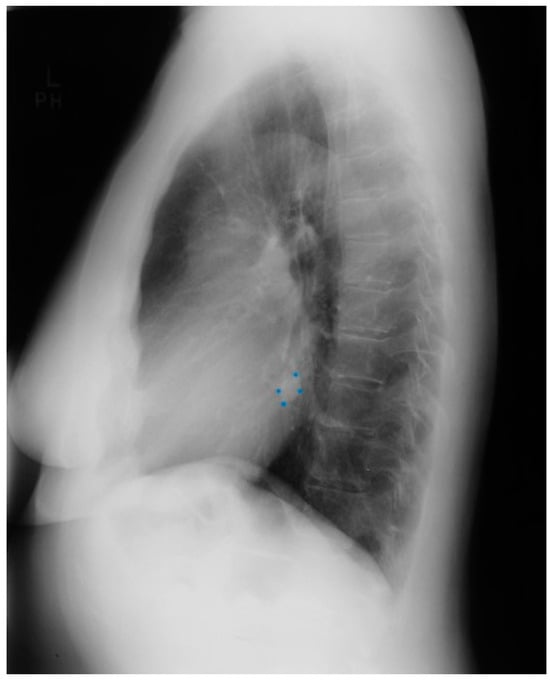

The anatomy and physiology of CCTGA without additional congenital heart disease is described in the section above. In the majority of cases of CCTGA, other congenital structural cardiac anomalies coexist. These concomitant anomalies are ventricular septal defect (VSD), which occurs 70% of the time (usually perimembranous), an Ebstein-like systemic tricuspid valve, and pulmonary stenosis (PS), which occurs 40% of the time [7]. Figure 13 and Figure 14 showcase representative chest X-rays. The primary complications of adult patients with CCTGA are systemic atrioventricular valve regurgitation and complete atrioventricular electrical conduction block (third degree AV block).

Figure 13.

Posteroanterior chest X-ray in congenitally corrected transposition of the great arteries in adulthood: This is a PA chest X-ray of a 41-year-old male who was diagnosed with congenitally corrected transposition of the great arteries (CCTGA) shortly after birth. He underwent surgical closure of a large atrial septal defect (ASD) while still under the care of a pediatric cardiologist. He remained asymptomatic and regular care was not continued as an adult. When he developed rapid atrial fibrillation with reduced functional capacity he sought medical attention and completed a chest X-ray. The image is well centered and the inspiration is good. There is mesocardia where the cardiac apex is pointing midline. The cardiothoracic ratio is <0.5. The bifurcation of the trachea demonstrates an obtuse angle between the main bronchi. This suggests left atrial enlargement, which likely accounts for the onset of atrial fibrillation. The left hilum is larger than expected for CCTGA, but this might be related to the previously-repaired ASD. The pulmonary vascularity is normal.